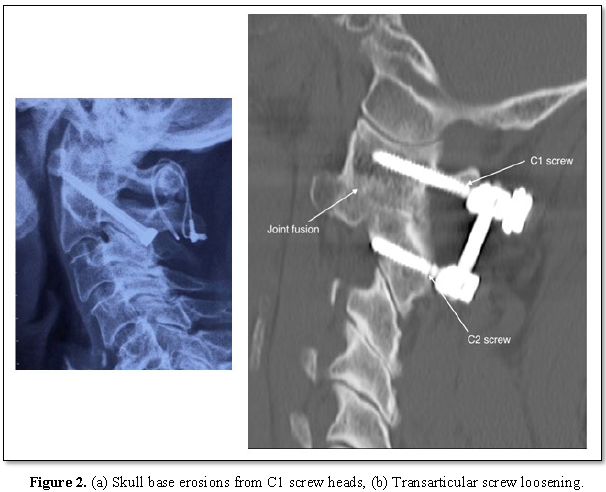

Mean NDI score prior to surgery was 72.2 which reduced to 18.9 post-operatively (Z=4.199, p<0.0005) (Table 1). Pre and post-operative range of movement measures were identical with lateral rotation most affected. Radiological fusion was shown in 21 patients (95.5%). 2 patients’ scans revealed skull base erosion around the head of the Harms screw (Figure 2a). One patient had a non-union with recurrence of pain 4 years post TAS fixation; CT demonstrated implant loosening and resorption of bone graft (Figure 2b). 21 of the 23 patients (91.3%) stated they would undergo the surgery again.

2 patients in our series had skull base erosions because of the proximity of the C1 screw heads to the inferior occiput (Figure 2a). One patient, a 71 year old female, underwent revision surgery one year following TAS fixation. The hardware was removed and replaced with lateral mass screws. Right sided neck pain recurred after one year; imaging showed stable fusion but significant skull base erosion (Figure 2a). C1 screws were removed and her pain improved. The second patient, a 66 year old female, developed right-sided suboccipital pain one year following the surgery. CT scan revealed similar skull base erosions, more marked on the right side.